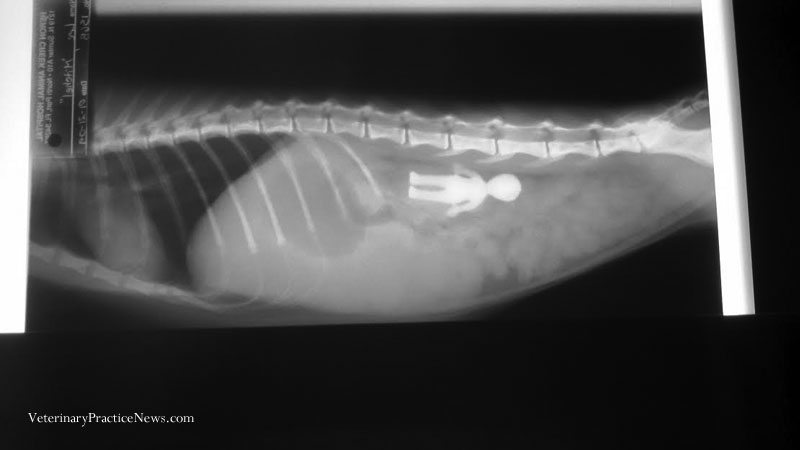

冠軍:青蛙柯密特(Kermit)

柯密特有牠特別偏好的「零食」──牠的主人發現牠會吃飼養箱裡的石頭,而X光片結果也證實了這個觀察,獸醫進行外科手術移除柯密特肚子裡的30多顆小石頭後,並沒有產生任何併發症,而牠的主人也明智的移除了箱子裡剩下的石頭。